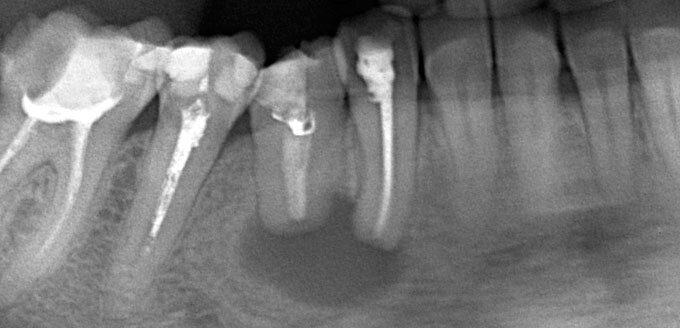

После сбора анамнеза врач осматривает зубодесневые карманы, коронки, мосты, пломбы, использует зонд, назначает инструментальную диагностику. Обязательно назначается рентгенография – только этот метод позволяет с точностью оценить новообразование.

В этом случае прицельный снимок редко достаточно информативен, чтобы врач принимал решение о дальнейшей тактике лечения. Ортопантомограмма позволяет оценить состояние всей челюсти и определить патологию в мягких тканях и каналах зубов, гайморовых пазухах. Но лучше всего определить размеры кисты, положение, спрогнозировать развитие и подготовиться к операции помогает компьютерная томография. С помощью КЛКТ врач получает 3D-снимок – детальное послойное трехмерное изображение патологии.